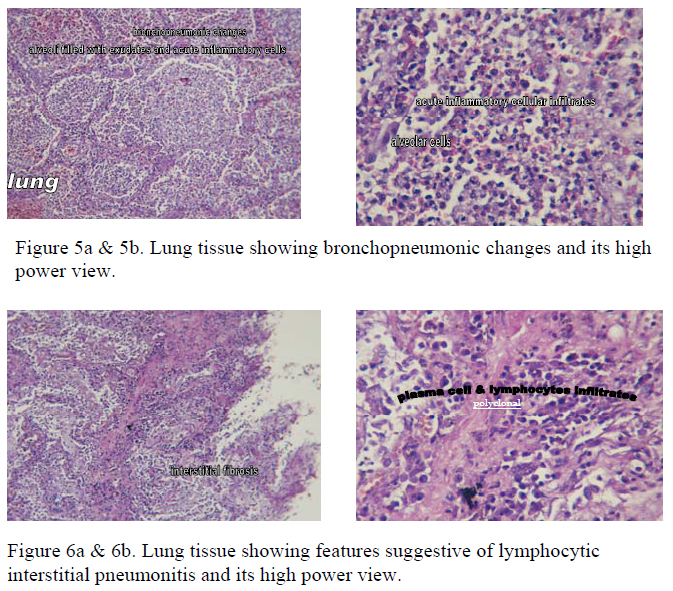

2. Marked pleural adhesion was present in both sides, more severe in right side. Both lungs showed congestion and oedema. Consolidation of lung parenchyma with reddish appearance was present esp. in RML and BLL (Fig. 5a & 5b). There were also areas with septae thickening and polyclonal lymphocytic and plasma cells infiltrates, suggestive of lymphocytic interstitial pneumonitis (Fig 6a & 6b).